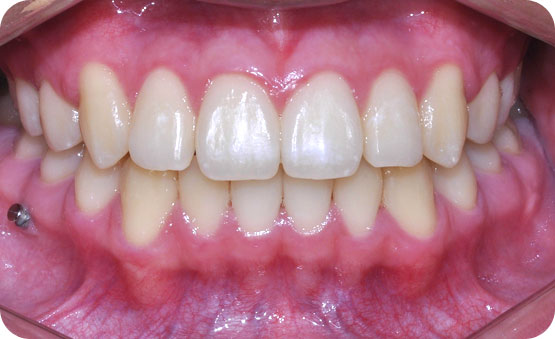

미니스크류를 이용한 하악골 돌출 비발치교정

Before

After